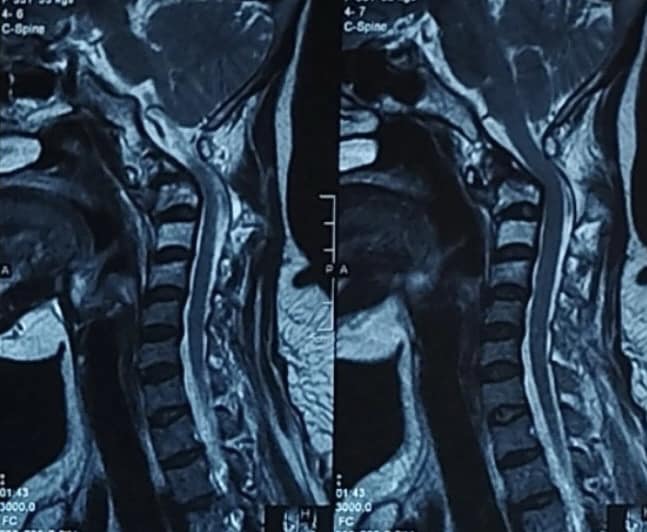

Với chẩn đoán ung thư phổi giai đoạn muộn, bệnh nhân V. đã được điều trị hoá chất, trong quá trình điều trị, bệnh tiến triển, di căn lên các đốt sống cổ C1, C2.

Sau 1 tháng, tình trạng khối u phổi được kiểm soát tốt, khối u cột sống cổ cao đã co nhỏ, lúc này bệnh nhân được tiến hành cố định cột sống cổ nhằm giải quyết tình trạng mất vững của người bệnh, phòng ngừa nguy cơ liệt tứ chi.

“Tổn thương tại vùng đốt sống cổ C1, C2 là những tổn thương khó xử lý, khó can thiệp bởi chứa những trung tâm rất quan trọng của tủy sống và não: Hành tủy, trung tâm hô hấp, vận động tứ chi,... bên cạnh đó cột sống cổ C1C2 còn có vai trò nâng đỡ hộp sọ, đây cũng là thách thức với chúng tôi khi điều trị”- TS.BS Nguyễn Đức Liên, Trưởng khoa Ngoại thần kinh Bệnh viện K chia sẻ.

Các bác sỹ khoa Ngoại thần kinh TS.BS Nguyễn Đức Liên, Trưởng khoa và Ths.Bs Nguyễn Thái Học, Ths.Bs Nguyễn Văn Linh đã phẫu thuật, ca mổ được chuẩn bị chu đáo từ việc kê tư thế, bởi chỉ cần cúi cổ hoặc ưỡn cổ quá mức cũng có thể làm tổn thương tủy. Các bác sỹ đã thực hiện các thao tác rất cẩn thận, can thiệp giải ép tủy sống khỏi chèn ép trước, sau đó nắn chỉnh và cố định cột sống cổ và xương sọ. Sau mổ 4 ngày người bệnh bắt đầu tập ngồi dậy và tập đi lại, có thể chỉ định dùng thuốc hóa chất duy trì sau 2-3 tuần.